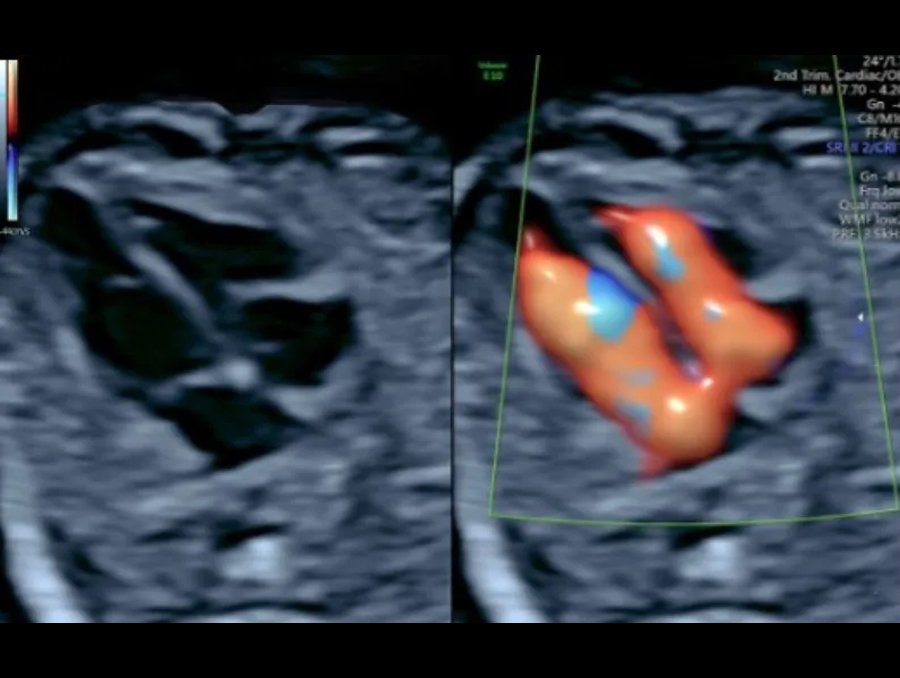

Fetal echo at Zenith Hospital, Nagpur, under the care of Dr. Manasi Thakur, can be performed in two ways:

Abdominal Echocardiography – Similar to a regular ultrasound, where a probe is placed on the abdomen to capture images.

Transvaginal Echocardiography – The probe is gently inserted into the vagina, usually recommended in the early stages of pregnancy for clearer imaging.